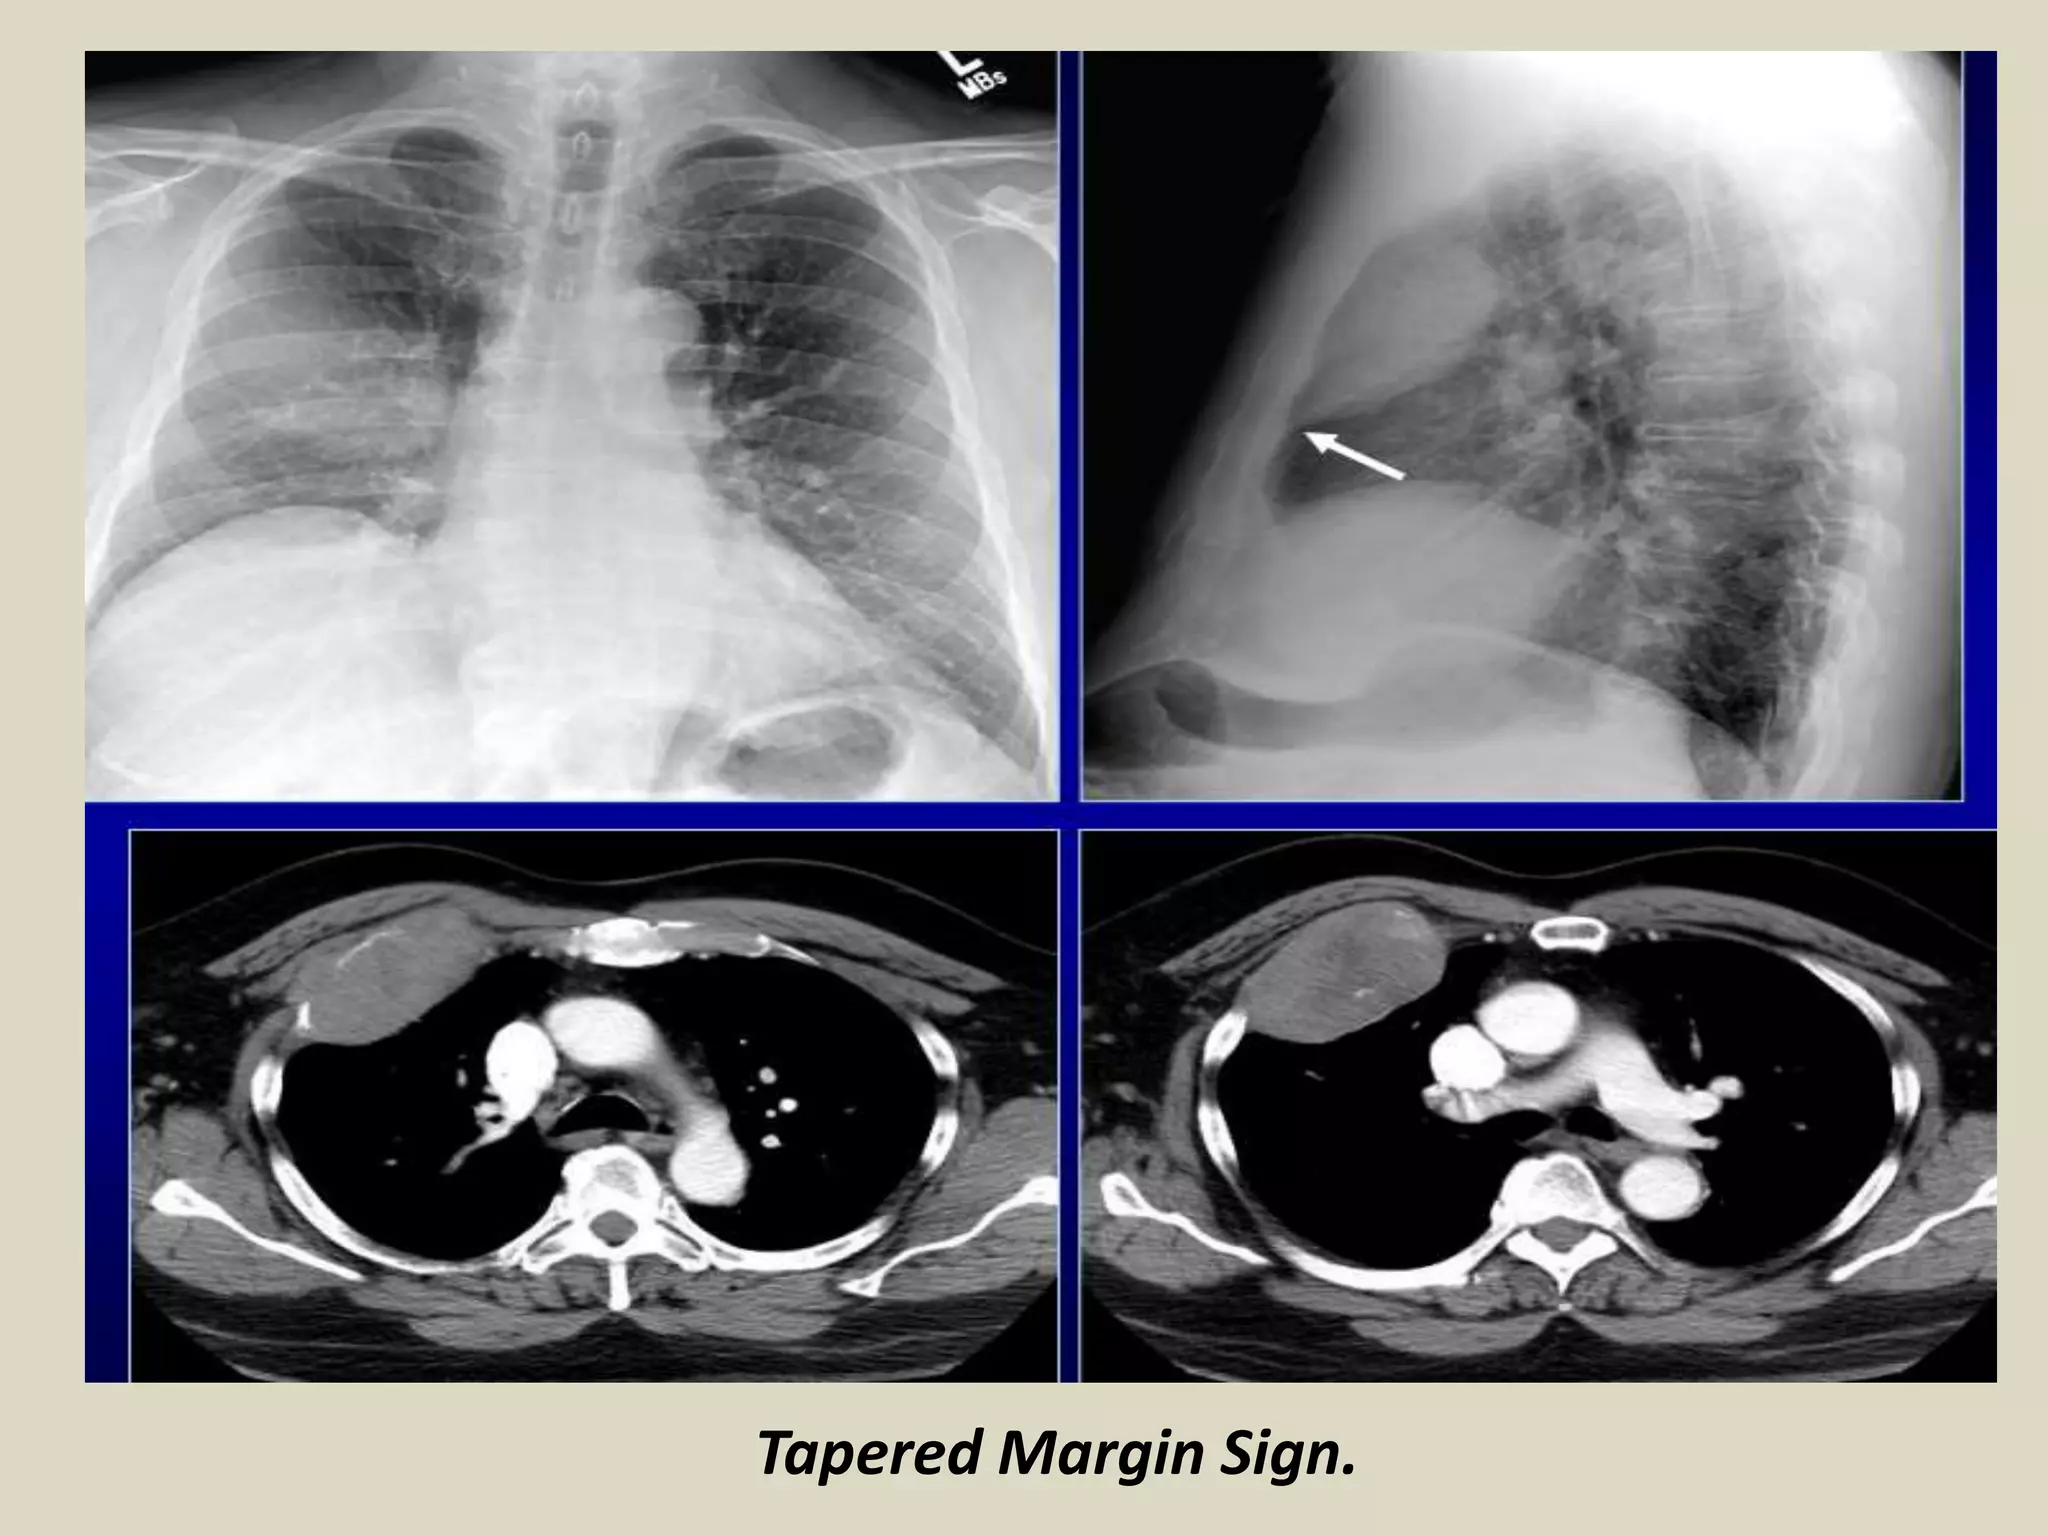

TAPERED MARGINS SIGN

Lesions in the chest wall, pleura or mediastinum have smooth tapered borders

and obtuse angles

While parenchymal lesions usually form acute angles

TAPERED MARGINS SIGN. Chest radiographs with schematic drawings. Mesothelioma and thymic lymphosarcoma.

Tapered Margin Sign.

. A lesion in the chest wall, pleural or mediastinum have

smooth tapered borders and obtuse angles.

. While parenchymal lesions usually form acute angles.

TAPERED MARGINS SIGN Lesionsin the chest wall, pleura or mediastinum have smooth tapered borders and obtuse angles While parenchymal lesions usually form acute angles TAPERED MARGINS SIGN. Chest radiographs with schematic drawings. Mesothelioma and thymic lymphosarcoma.

Tapered Margin Sign. .A lesion in the chest wall, pleural or mediastinum have smooth tapered borders and obtuse angles. . While parenchymal lesions usually form acute angles. Tapered Margin Sign.